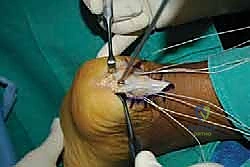

- فصل الوتر (الجزئي أو الكلي): للوصول إلى النتوء العظمي والتكلسات، يضطر الجراح لفصل جزء من وتر أخيل من مكان ارتكازه.

- استئصال تشوه هاغلوند والتكلسات: باستخدام أدوات جراحية دقيقة، يتم قص وإزالة النتوء العظمي البارز بالكامل، وتسوية سطح عظم الكعب لضمان عدم احتكاكه بالوتر مستقبلاً. كما يتم إزالة أي تكلسات عظمية نامية داخل ألياف الوتر نفسها.

- التنضير (Debridement): يقوم الجراح بقص وإزالة كافة الأنسجة الميتة، المتهالكة، والتنكسية من الوتر، مع الحفاظ على الألياف السليمة والقوية.

- إعادة التثبيت باستخدام الخطاطيف (Suture Anchors): هذه هي المرحلة الأهم والتي تعتمد على التكنولوجيا الحديثة. يتم زرع خطاطيف دقيقة (مصنوعة من التيتانيوم أو مواد قابلة للامتصاص) داخل عظم الك